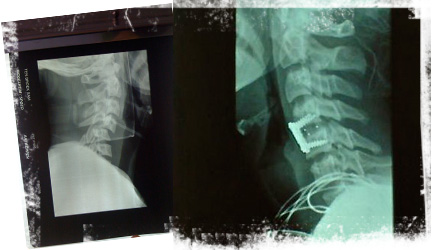

sam_intensive_1 Sam heeft een ernstig sportongeval gehad. Hij is in zijn turnclub bij het trampolinespringen verkeerd neergekomen en heeft zijn nek gebroken tussen de 4de en 5de wervel. Hij is meteen volledig verlamd. Hij wordt onmiddellijk geopereerd maar de vooruitzichten zijn deprimerend. Hij krijgt sondevoeding en is aangesloten op heel veel apparaten.

sam_grapjesSam heeft nog steeds hoge koorts en heel erge keelpijn (door de snee van de operatie, door het 'plaatje' om zijn wervels weer op hun plaats te zetten, door de tracheotomie, door de sonde die door zijn neus en keel naar zijn maag gaat, door het 'slotje' dat rechtstreeks in een halsader zit en waarvoor hij zware antibiotica krijgt). Hierdoor kan hij moeilijk slikken, maar hij moét eten anders verzwakt hij nog meer en kan de sonde niet uit zijn neus. Hij doet zijn uiterste best!